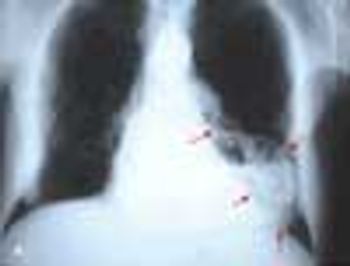

An 80-year-old man complains of lancinating pain in his right axilla and chest that began 2 days earlier and has kept him awake at night. He has had no fever, cough, sputum production, dyspnea, or symptoms suggestive of congestive heart failure.